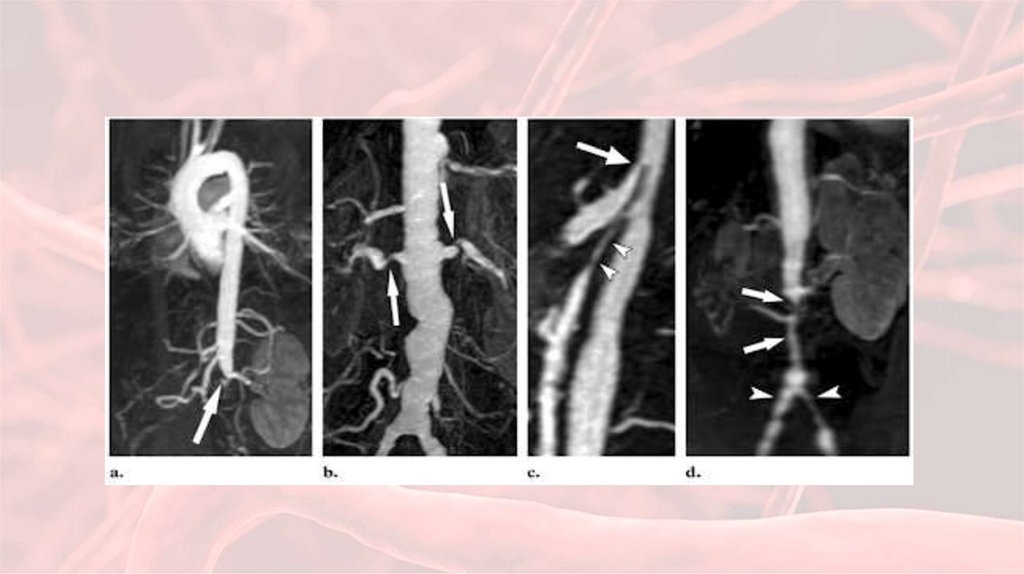

47. Чем болеет пациентка?

• Объективно: систолический шум над левой

почечной артерией

52. Клинические исследования:

1. Исследование

пульса, АД на обеих

руках и ногах,

аускультация сосудов

различных регионов.

2. Ангиография.

3. Ультразвуковое

дуплексное

сканирование,

компьютерная и

магнитнорезонансная

томография.

53. Классификационные критерии артериита Такаясу (W.P. Arend et al., 1990)

6. Изменения при ангиографии (сужение просвета или окклюзия аорты, ее крупных ветвей в проксимальных

отделах верхних и нижних конечностей, не связанное с атеросклерозом, фибромускулярной дисплазией и др.).